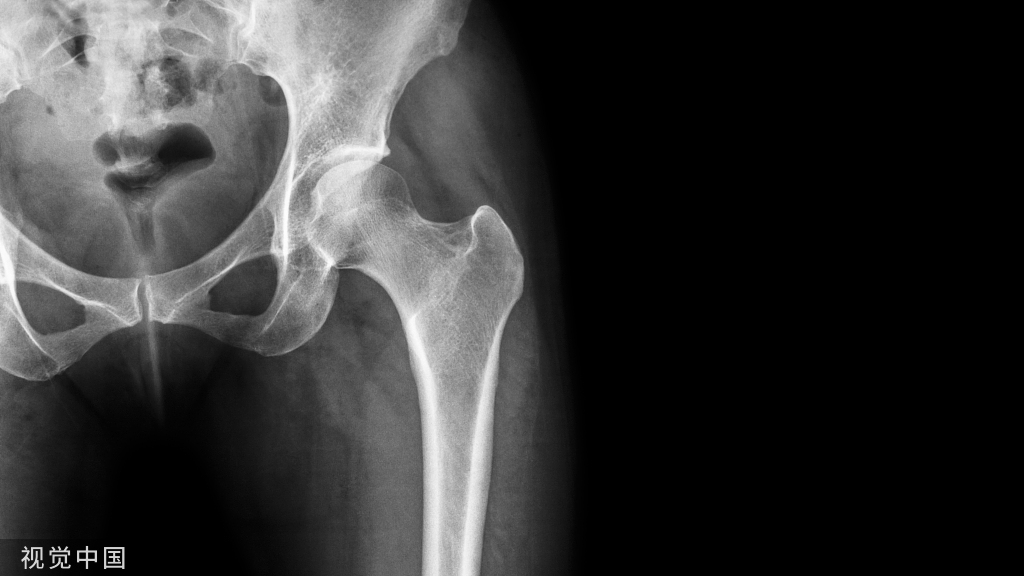

图4:35岁男性,钩钢板固定,术前术后影像片。